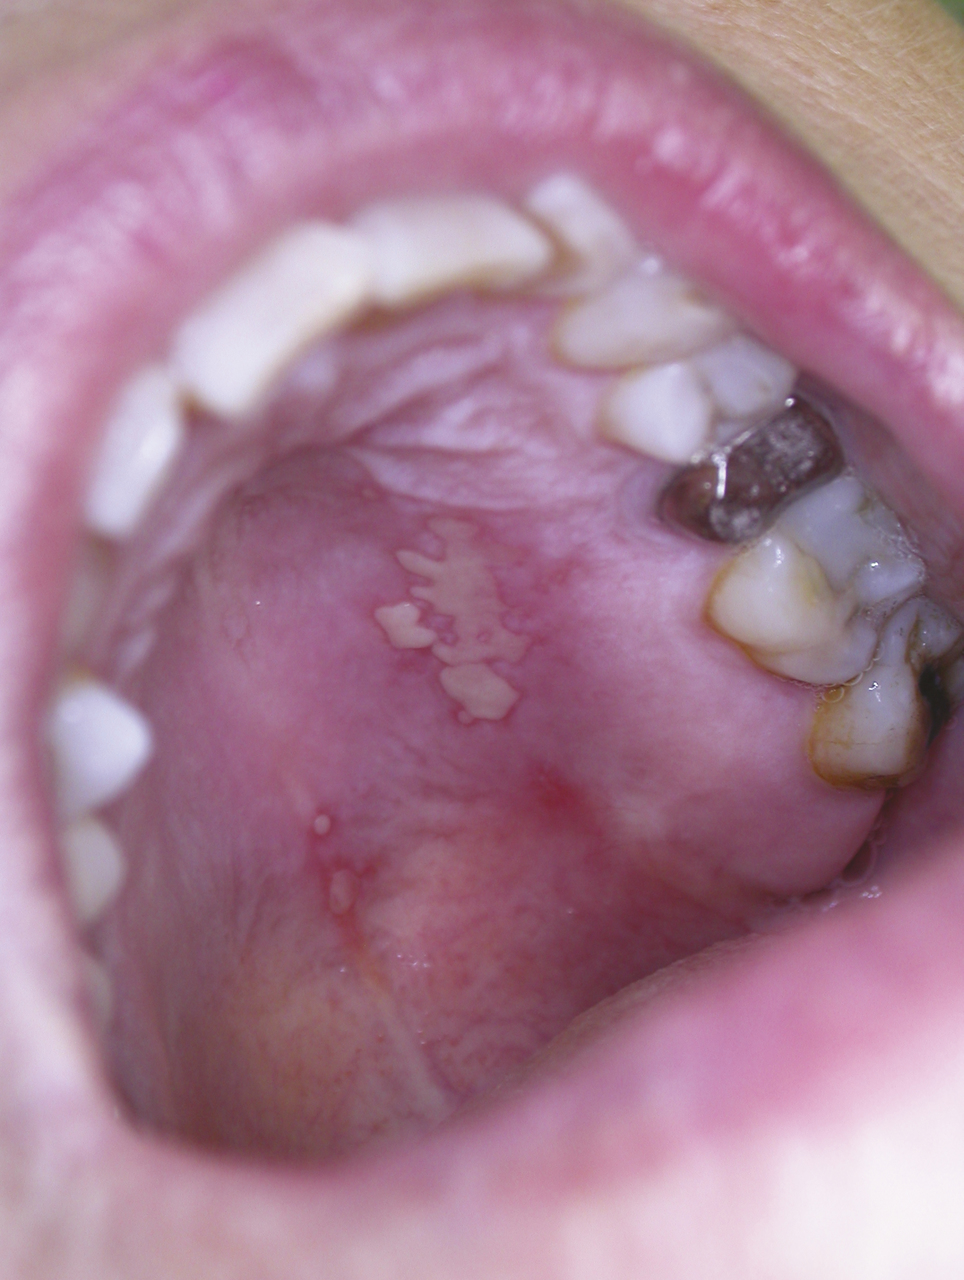

Les papillomavirus humains qui ont un tropisme pour les kératinocytes des épithéliums malpighiens sont responsables de tumeurs bénignes (verrues, papillomes, condylomes) ; certains d’entre eux sont oncogènes (col de l’utérus, carcinomes épidermoïdes pharyngolaryngés) ; leur implication dans la survenue de carcinomes épidermoïdes de la cavité buccale n’est pas démontrée. Les papillomes sont des élevures de quelques millimètres de diamètre, indolores à surface kératosique (fig. 7 ), des verrues digitales sont parfois à l’origine de l’auto-inoculation. Les condylomes acuminés sont rares sur la muqueuse buccale, leur transmission est sexuelle. L’évolution spontanée est variable, ils persistent ou se multiplient mais peuvent également régresser spontanément. La présence de papillomes multiples (fig. 8 ) fait rechercher une immunodépression. Le traitement repose sur la destruction des lésions (chirurgie, laser CO2) ; les récidives sont possibles.

Les papillomavirus humains qui ont un tropisme pour les kératinocytes des épithéliums malpighiens sont responsables de tumeurs bénignes (verrues, papillomes, condylomes) ; certains d’entre eux sont oncogènes (col de l’utérus, carcinomes épidermoïdes pharyngolaryngés) ; leur implication dans la survenue de carcinomes épidermoïdes de la cavité buccale n’est pas démontrée. Les papillomes sont des élevures de quelques millimètres de diamètre, indolores à surface kératosique (